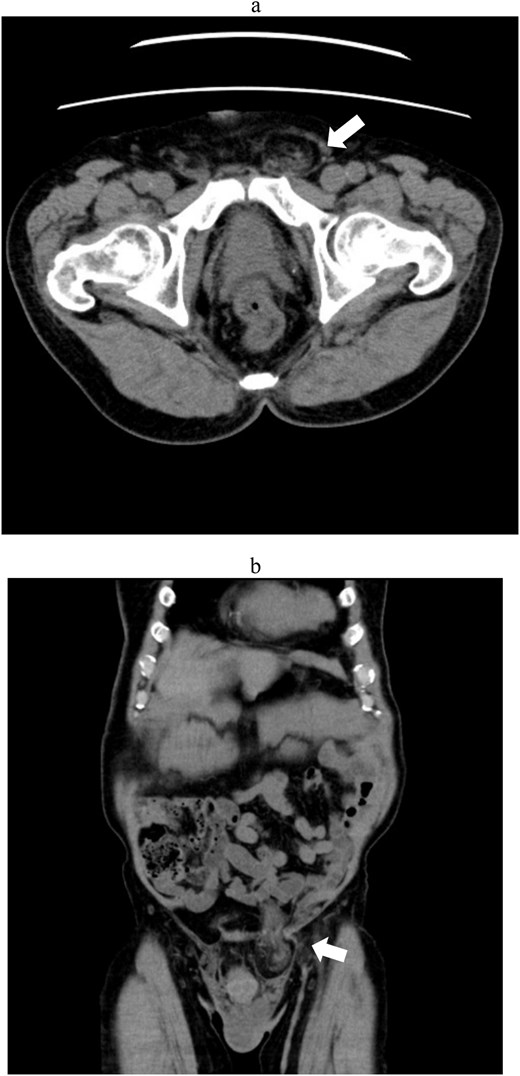

A 77-year-old man (162 cm, 71.8 kg) with hypertension and benign prostatic hyperplasia presented with a left groin bulge. He had undergone open anterior mesh plug repair 15 years earlier using two L-size plugs for left direct and indirect hernias (EHS classification: M1, L1) [3]. Current examination and prone CT with abdominal compression revealed a recurrent left inguinal hernia containing omentum (Fig. 1a and b).

Abdominal computed tomography showing a recurrent left inguinal hernia (arrows) containing omental tissue. (a) Axial view. (b) Coronal view.